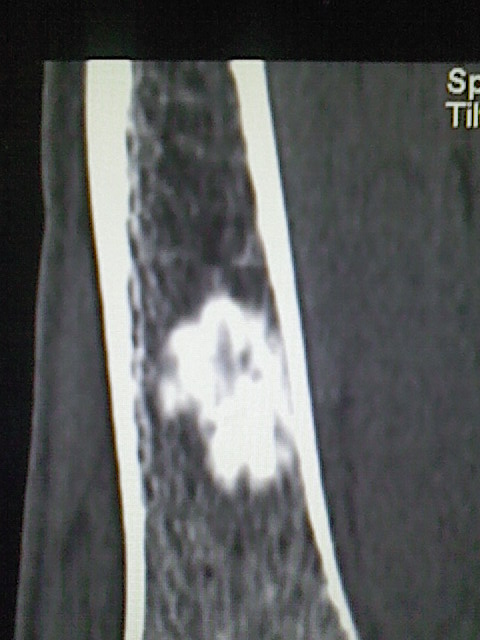

可见瘤巢,考虑骨样骨瘤

内生骨瘤可能性大,不知病人有何症状,不除外骨样骨瘤

不排除骨样骨瘤可能,建议上传骨窗。

良性骨肿瘤,以内生软骨瘤或骨纤维瘤可能大。请上传骨窗。